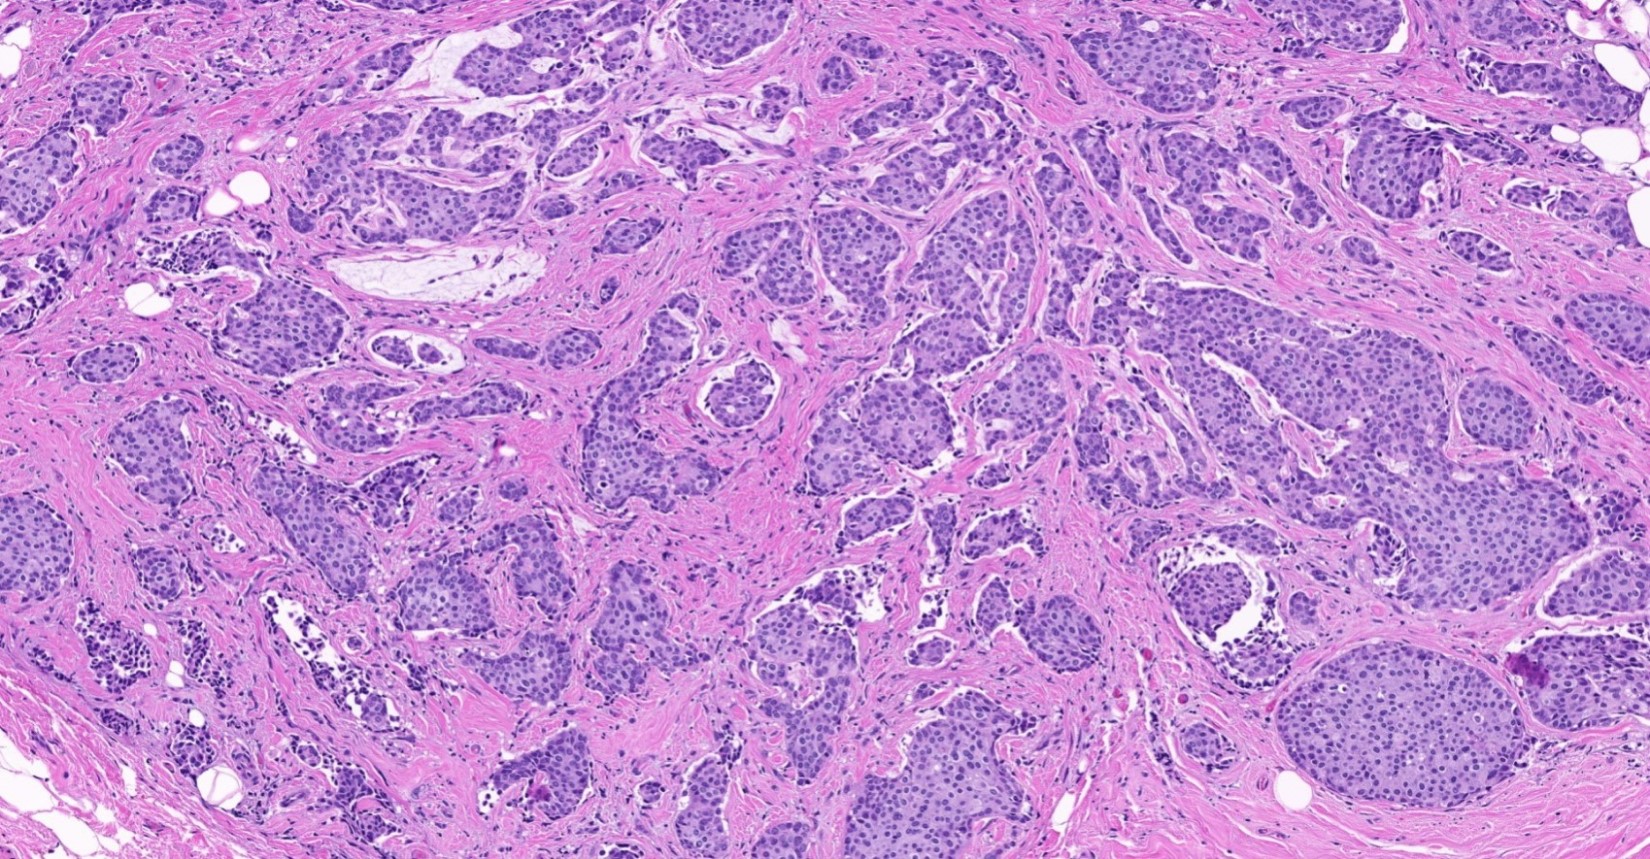

Microscopic (histologic) description

- Histological features of IBC NST vary considerably from case to case and even within the same case

- Architecture varies from sheets, nests, clusters, cords or individual cells (but lacks the cytomorphological characteristics of invasive lobular carcinoma)

- 2 distinct growth patterns exist:

- Large and solid nests or syncytial infiltrative growth pattern with little associated stroma and an expansive growth that compresses the surrounding stroma (e.g., most basal-like breast cancers)

- Basal-like or medullary-like patterns:

- These include breast carcinomas previous described as medullary-like carcinoma or carcinoma with medullary features, as well as basal-like carcinoma

- These tumors typically show high histological grade, a prominent tumor associated lymphocytic (TIL) infiltrate, a triple negative phenotype and often have basal-like molecular profiles

Microscopic (histologic) images

Contributed by Julie M. Jorns, M.D., Kristen E. Muller, D.O., Gary Tozbikian, M.D. and Emad Rakha, M.D.